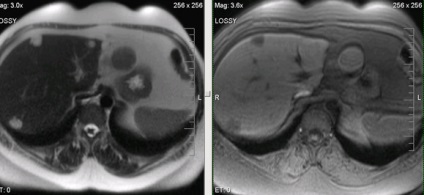

Natív és postkontrastnye MR hemangioma diffúz típusú amplifikációs.

MRI az UCP natív és dinamikus kontrasztos tanulmány. MRI dinamikus kontrasztanyagos megbízhatóan érzékeli, és lehetővé teszi egyedi képződése jellemzi a máj, mint a csomóponti noduláris hiperplázia.

Noduláris hiperplázia Máj

MRI képalkotó hepatocelluláris adenoma a máj